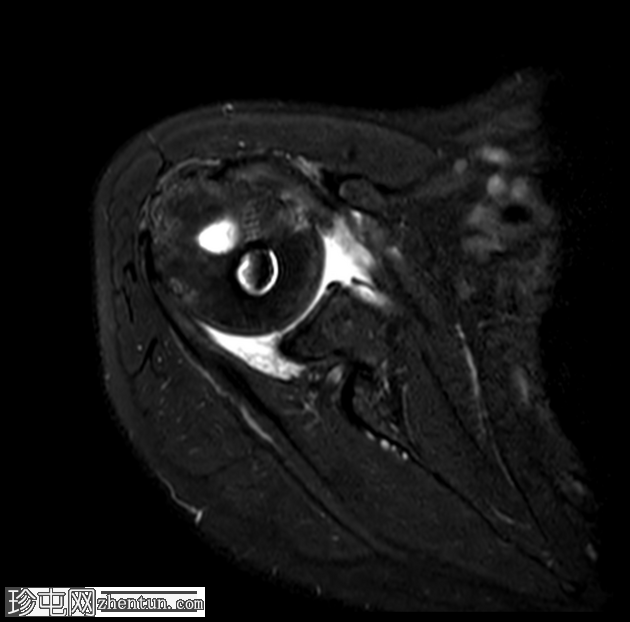

轴位T2加权像

脂肪抑制像

T2加权像显示近端锚钉周围有液体信号,提示锚钉松动,这并非正常的术后表现,提示骨整合不牢固。

MRI 诊断锚钉松动的依据是,在骨内锚钉周围可见晕圈状液体信号。